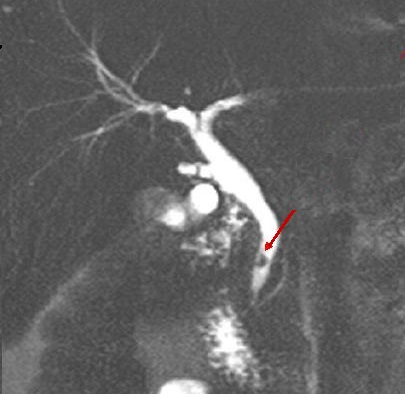

Image radiologique cholangio

- IRM de calcul choledocien et de voie biliaire en

coupe frontal , pondere sur T2 . La bile , le

contenue dans voie biliaire , d'origine de l'eau

sont tres intense ( hypersignal ) et les calcules du

canal choledocque se presence en forme

lacunaire intraluminal sont tres hypointense |

|

-IRM de voie biliaire et de calcul choledocien

recontructive en 3D . Voie biliaire pricipale et des

branches intrahepatiques est tres nette . Le

calcul du canal choledoque est en aspect lacunaire

arrondie a hypointense situe a la portion inferieure

du canal choledoque ( fleche rouge ) . |